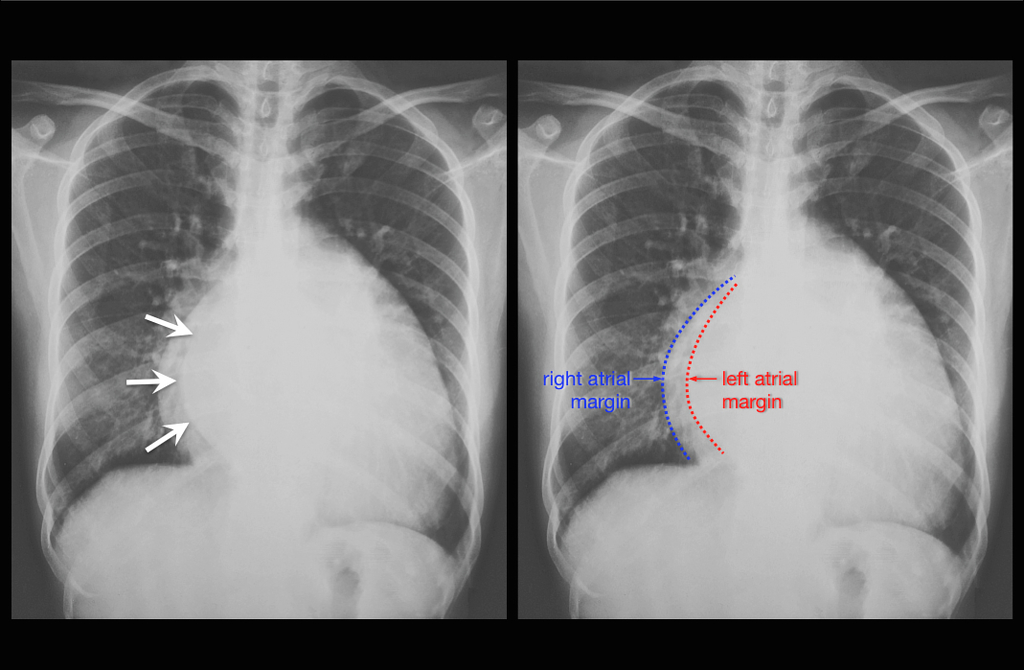

Biatrial enlargement on CXR All About Cardiovascular System and Disorders Heart Shadow X Ray Potential causes of enlargement of the cardiac silhouette include: The heart is enlarged, the apex is rounded, the right atrium prominent (1) and the pulmonary arteries are dilated. Cardiac silhouette refers to the outline of the heart as seen on frontal and lateral chest radiographs and forms part of the. Diligence is required to maximise the chance of detection of. Heart Shadow X Ray.